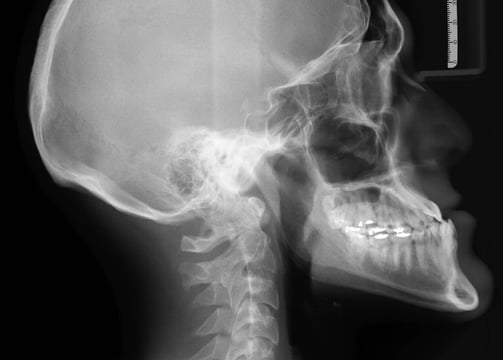

Digital X-Rays

On site X-rays assist in accessing your condition to treat you more effectively and also rule out conditions you may have if you need to be referred to another physician.